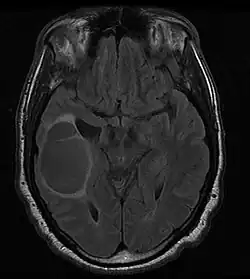

Skąpodrzewiak (łac. oligodendroglioma) – nowotwór złośliwy ośrodkowego układu nerwowego wywodzący się z komórek gleju skąpowypustkowego (oligodendrocytów). Jest nowotworem o pośredniej złośliwości (II stopnia według WHO); wariant anaplastyczny (skąpodrzewiak anaplastyczny) jest guzem o wysokiej złośliwości (III stopnia według WHO). Skąpodrzewiak rozwija się najczęściej w płacie czołowym.

Obraz kliniczny wynika z lokalizacji guza. Ponieważ nowotwór charakteryzuje się powolnym tempem wzrostu, objawy rozwijają się powoli i mogą na wiele lat wyprzedzać rozpoznanie choroby. Jednym z dominujących objawów guza zlokalizowanego w płacie czołowym (50–65%) jest padaczka. Drugą pod względem częstości lokalizacją jest płat skroniowy.